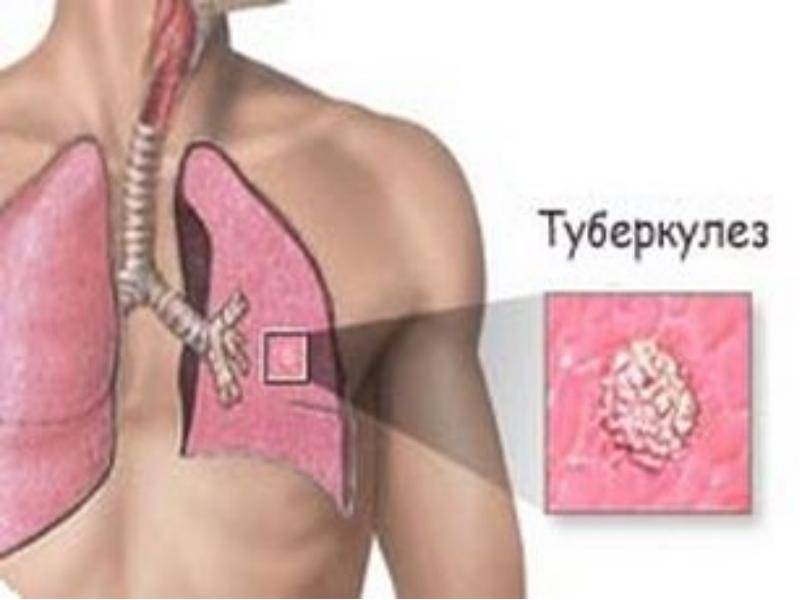

Симптомы туберкулеза: Как распознать и что делать

Раздел: Визуальные уроки